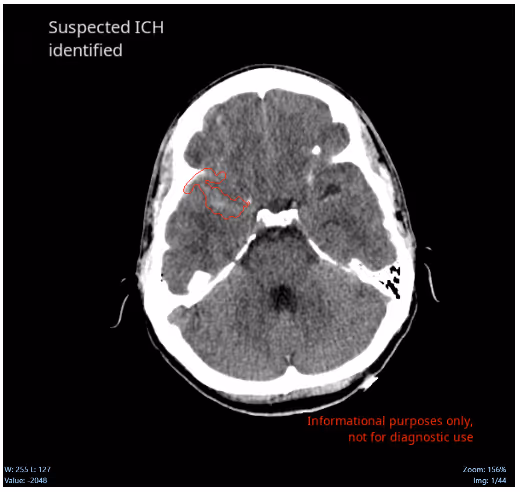

At 7:00 AM the attending radiologist reviewed the case and also observed a subtle acute traumatic subarachnoid hemorrhage.If CINA-ICH was deployed at this hospital, in less than 1minute after the NCCT acquisition, a new DICOM series would have been added to the study with the suspected ICH identified by the software and the case would have been prioritized helping the fellow into his diagnosis.

ConclusionGiven the large volume of cases performed daily, which is only increasing, it is important to have a second set of eyes to help identify and triage urgent cases. Missed findings are particularly prone during the evening, at the end of shifts, and on weekends. In this situation, a tool such as CINA-ICH can improve the diagnosis and treatment of patients because treatment decisions could have begun earlier.Note: Segmentation is currently available only for use in the UE. See Avicenna outputs documents for more information.Intracranial hemorrhages (ICH) affect over two million people worldwidewith a 40-50% patient mortality rate within one month, and 80% disability despite aggressive care.Quick and accurate early diagnosisof ICH mayfacilitate a prompt therapeutic response, allow fast decision-making, and ultimately improve outcomes.CINA-ICH uses deep learning to identify suspected intracranial hemorrhageand prioritizes those cases in the worklist, dramaticallyreducing turnaround time for head traumaand stroke patients.Interested in deploying CINA-ICH at your health facility? Contact the Ferrum Health team to learn more.